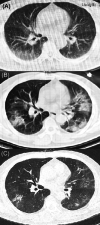

Co-infection of SARS-CoV-2 and HIV in a patient in Wuhan city, China